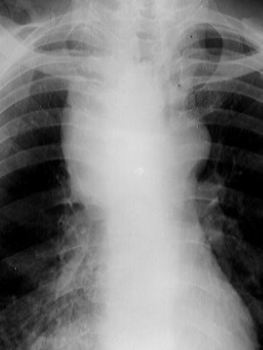

Rx toracică, incidență P-A

DESCRIERE:

la niv. întregului hemitorace drept → opacitate extinsă, nesistematizată, de intensitate mare, omogenă

caracter expansiv → împinge traheea și mediastinul de partea opusă

diafragm deplasat în jos

lărgirea spațiilor intercostale

umplerea spațiului costo-diafragmatic

DX: pleurezie masivă

DD: atelectazie → caracter retractil